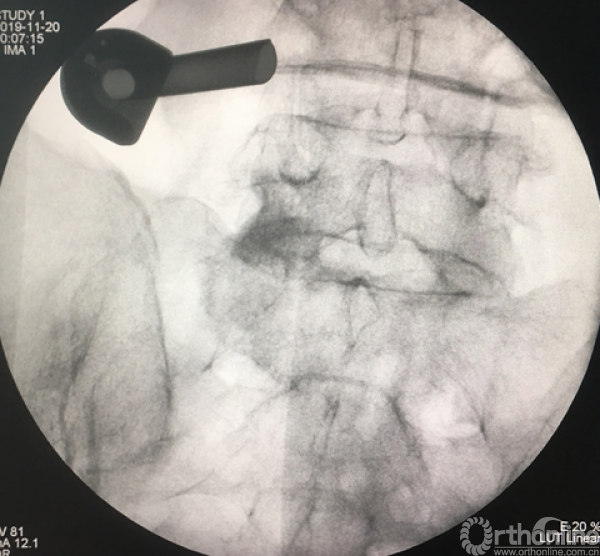

消毒前,给予椎间隙定位

放入工作套管

正侧位透视确定责任节段